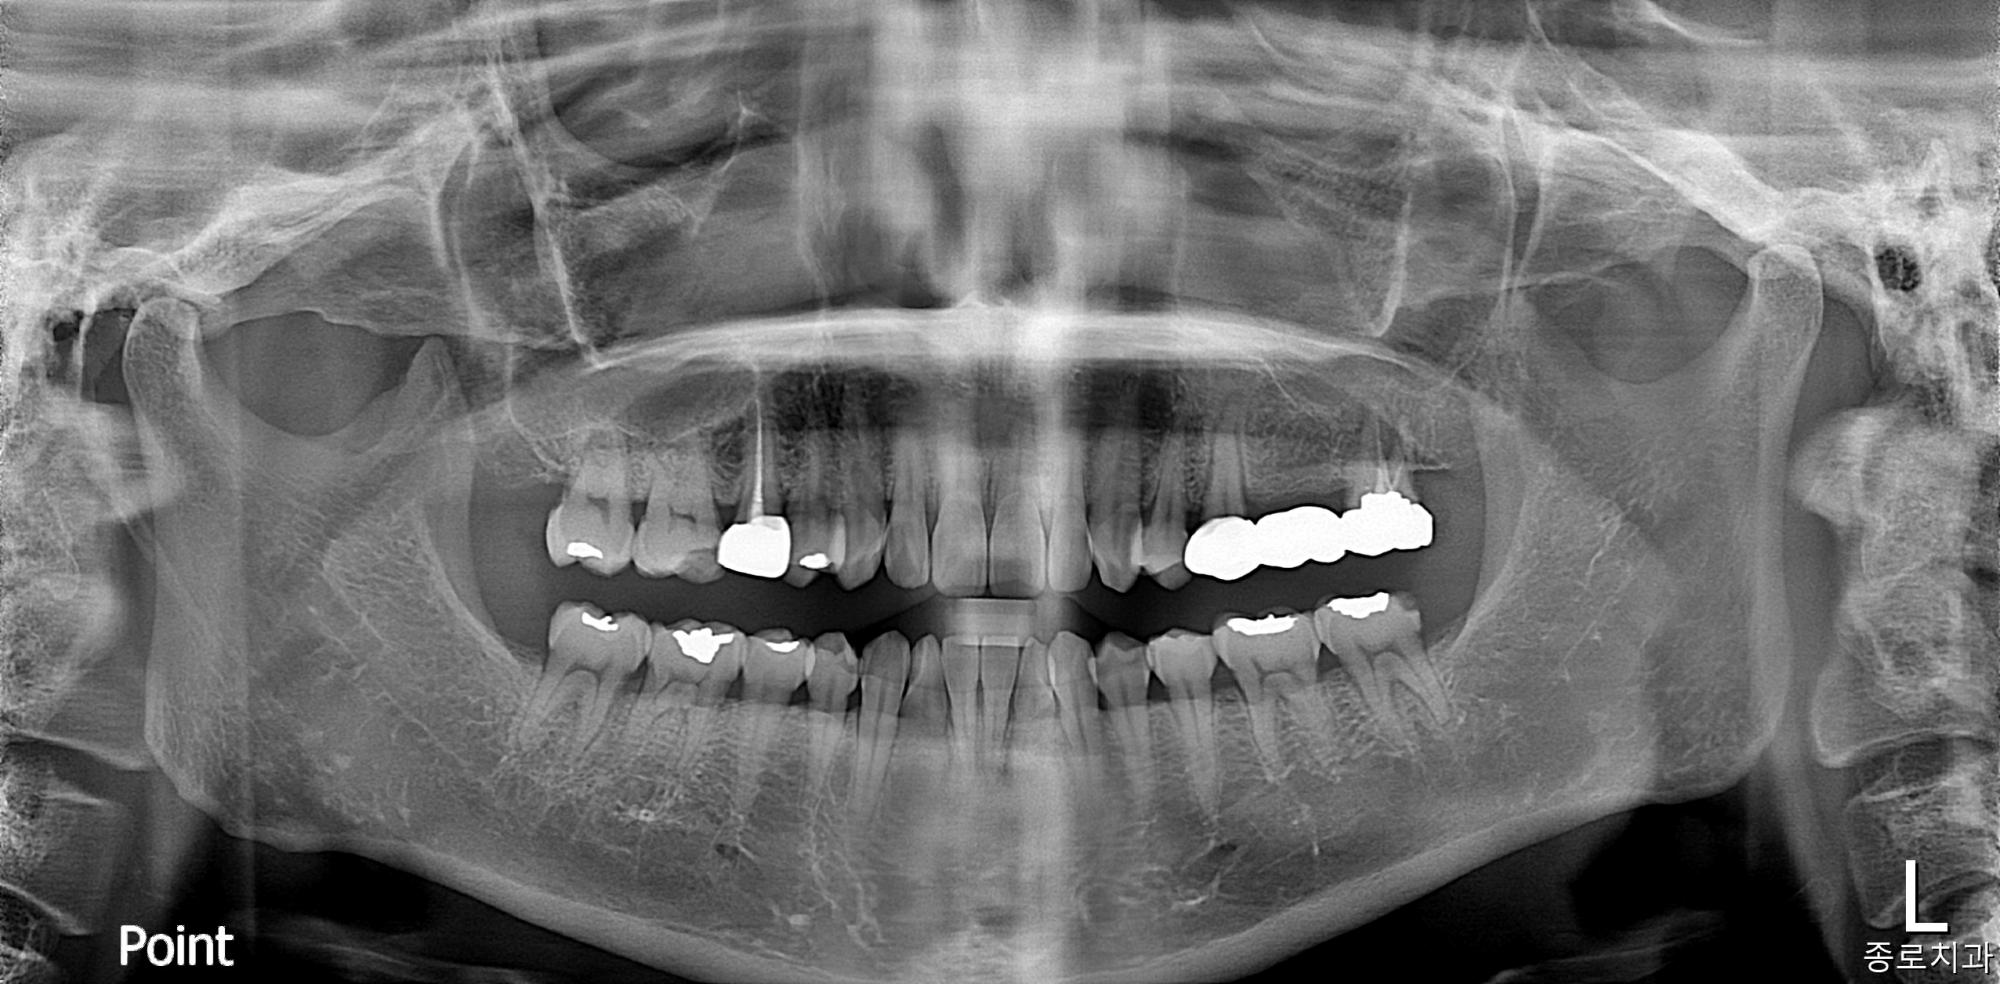

전/후사진

전/후 사진갤러리